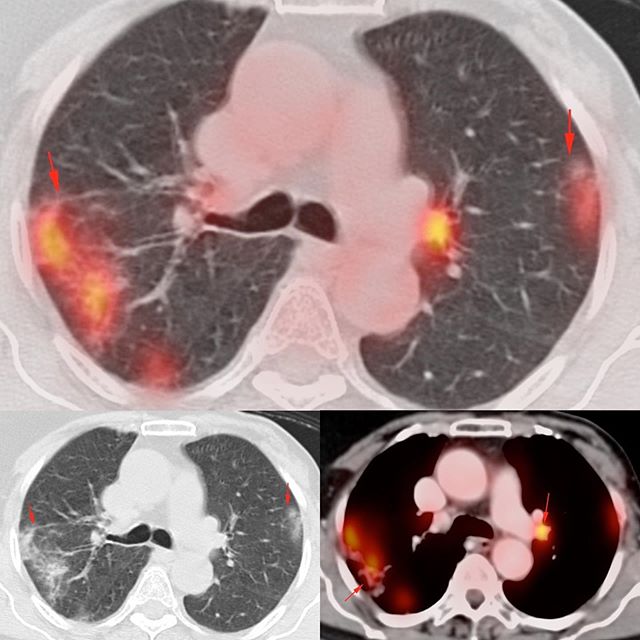

This 59-years old lady came for a follow-up PET/CT for Ca breast evaluation. She had no respiratory symptoms.

The lung shows typical findings of COVID-19 with uptake on the PET. Almost all patients with incidental COVID-19 show some level of activity, which likely lasts for some time, even after the RT-PCR becomes negative. In these patients, we never really know at what stage of the disease they are when we pick up these findings on PET. Some are tested, some not, some are RT-PCR positive, some not.

Almost all of them also have small active nodes, as we see in the left hilum in this patient.

We have to be careful, especially with less typical patterns, of not confusing COVID-19 with chemotherapy related lung injury.